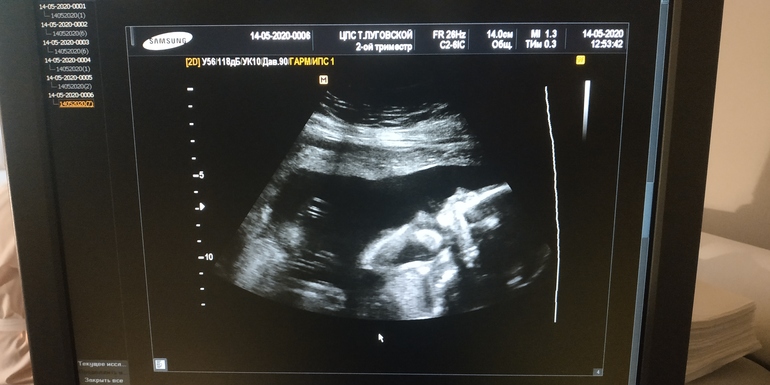

УЗИ, КТГ, доплерУвидела сегодня нашу красотульку на УЗИ 💕 она забилась в уголочек)) и сосала кулаки😆 и такая стесняшка, личико закрывала..) Лежит головой вниз.. Похожа снова не на меня🤣

Доктор папе сделал крупным планом фото причинного места😆 папа спокоен, что это точно девочка)

Всё у нас отлично, по срокам прям день в день как по месячным) так что ждём-с 22-23.09)))